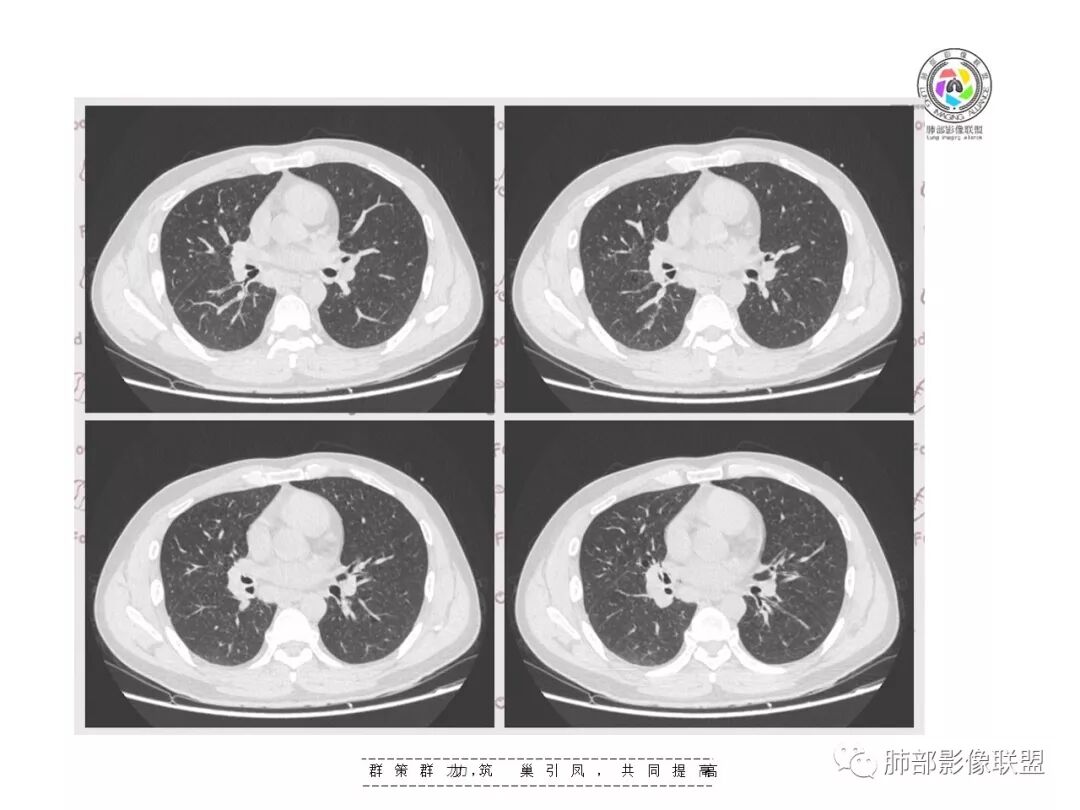

【影像资料】

张帅,首医附属潞河医院呼吸科:右肺下叶支气管开口明显狭窄,外基底段远端实变,内可见支气管征,周围可见弥漫结节样变,周围毛玻璃影,小叶间隔增厚,部分支气管壁不规则增厚,部分肺野可见小囊性变,壁部分增厚,右肺门明显增大,病灶与胸膜脂肪间隙增大,考虑恶性病变,腺癌。

王秀仙东宁市第二人民医院影像科:晨读:右肺下叶实变及磨玻璃影,边缘有收缩有膨隆,部分支气管进入扭曲扩张,磨玻璃影边缘清晰,实变影明显强化,内可见血管造影征,纵膈及肺门淋巴结肿大并强化,考虑粘液腺癌。

登封市三康医院(刘权威):右下肺肺不张,磨玻璃影,边缘清楚,空气支气管征,增强有强化,纵膈及右肺门淋巴结肿大并强化,考虑恶性肿瘤,粘液腺癌可能。

这是支气管扩张,老病灶,周围实变不明显,按理应该独立出来

下叶外基底段为主实变,周围GGO

这个病灶很有特色

分布:沿支气管段、亚段朝外蔓延分布

实变+GOG

实变区边缘收缩,支气管走形自然

但是我们也可以看到实变区很多地方没看到支气管,也就是支气管在实变区分布不均匀,提示有些地方支气管腔内有物质填塞,显示不清

GGO边界大部分不清楚,内有树芽征,中央间质均匀增厚